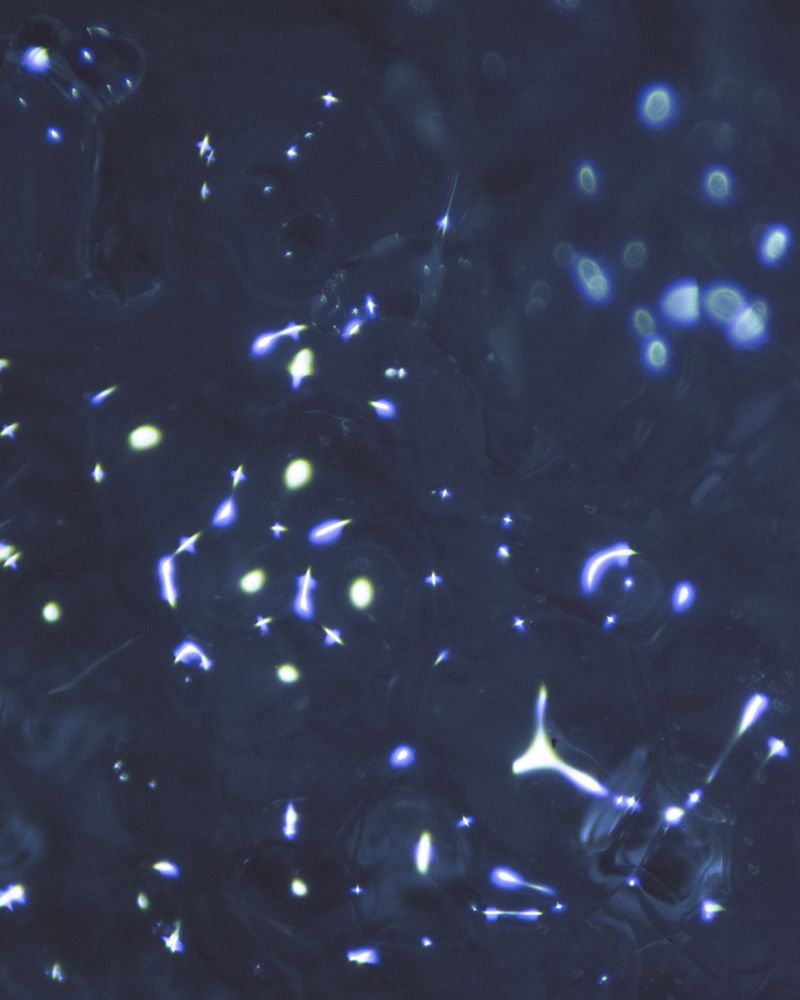

At the moment of fertilization, the egg releases chemical signals that attract the ideal spermatozoid, the most compatible, to its center. Over the next two weeks, by some inexplicable chance, it’s possible that the fertilized egg will divide into two exactly equal zygotes, and it’s at that moment that the gestation of monozygotic twins will begin, two beings with the same DNA chain and genetic information.

Las dos hebras (The Two Strands) seeks to understand, through history and metaphor, the other who is me, returning to that miniscule moment that gives way to my origin and that of my twin. I try to understand, decipher, and imagine it. My search has centered on the study of genetic history from the time of Pythagoras and that of the mystical sperm that gathers secret instructions on its journey throughout the body; on Aristotle who sustained that hereditary information was not found in the matter but in the message, like that of the drawings of the beaks of mockingbirds and Darwin’s tree of life. I have spent a great deal of time considering these events, recreating in my mind the human process for discovering oneself. I was accompanied by the work of Mendel, who obsessively cultivated and selected almost 400,000 seeds, hoping to find those that would produce identical descendants. I investigated the wet lab of Rosalind Franklin, British chemist and crystallographer, her life dedicated to science, and her discoveries that went unrecognized. Rosalind worked on deciphering the codes of nature, of crystals, and of invisible structures. She was the first to contemplate the image of an enigmatic molecule capable of containing hereditary information, what seemed to be the secret of life.

In Las dos hebras, I combined archival images from the study of genetics, diagnostic images of my genes and those of my twin, photographs of monozygotic twins, microscopic photographs that were taken in science and fertility labs, and images with poetic symbols that, as a whole, seek to establish contact with other people, whether twins or not, who may arrive at a place to question what in this alphabet, reflexive code, or mirrored code makes us human.